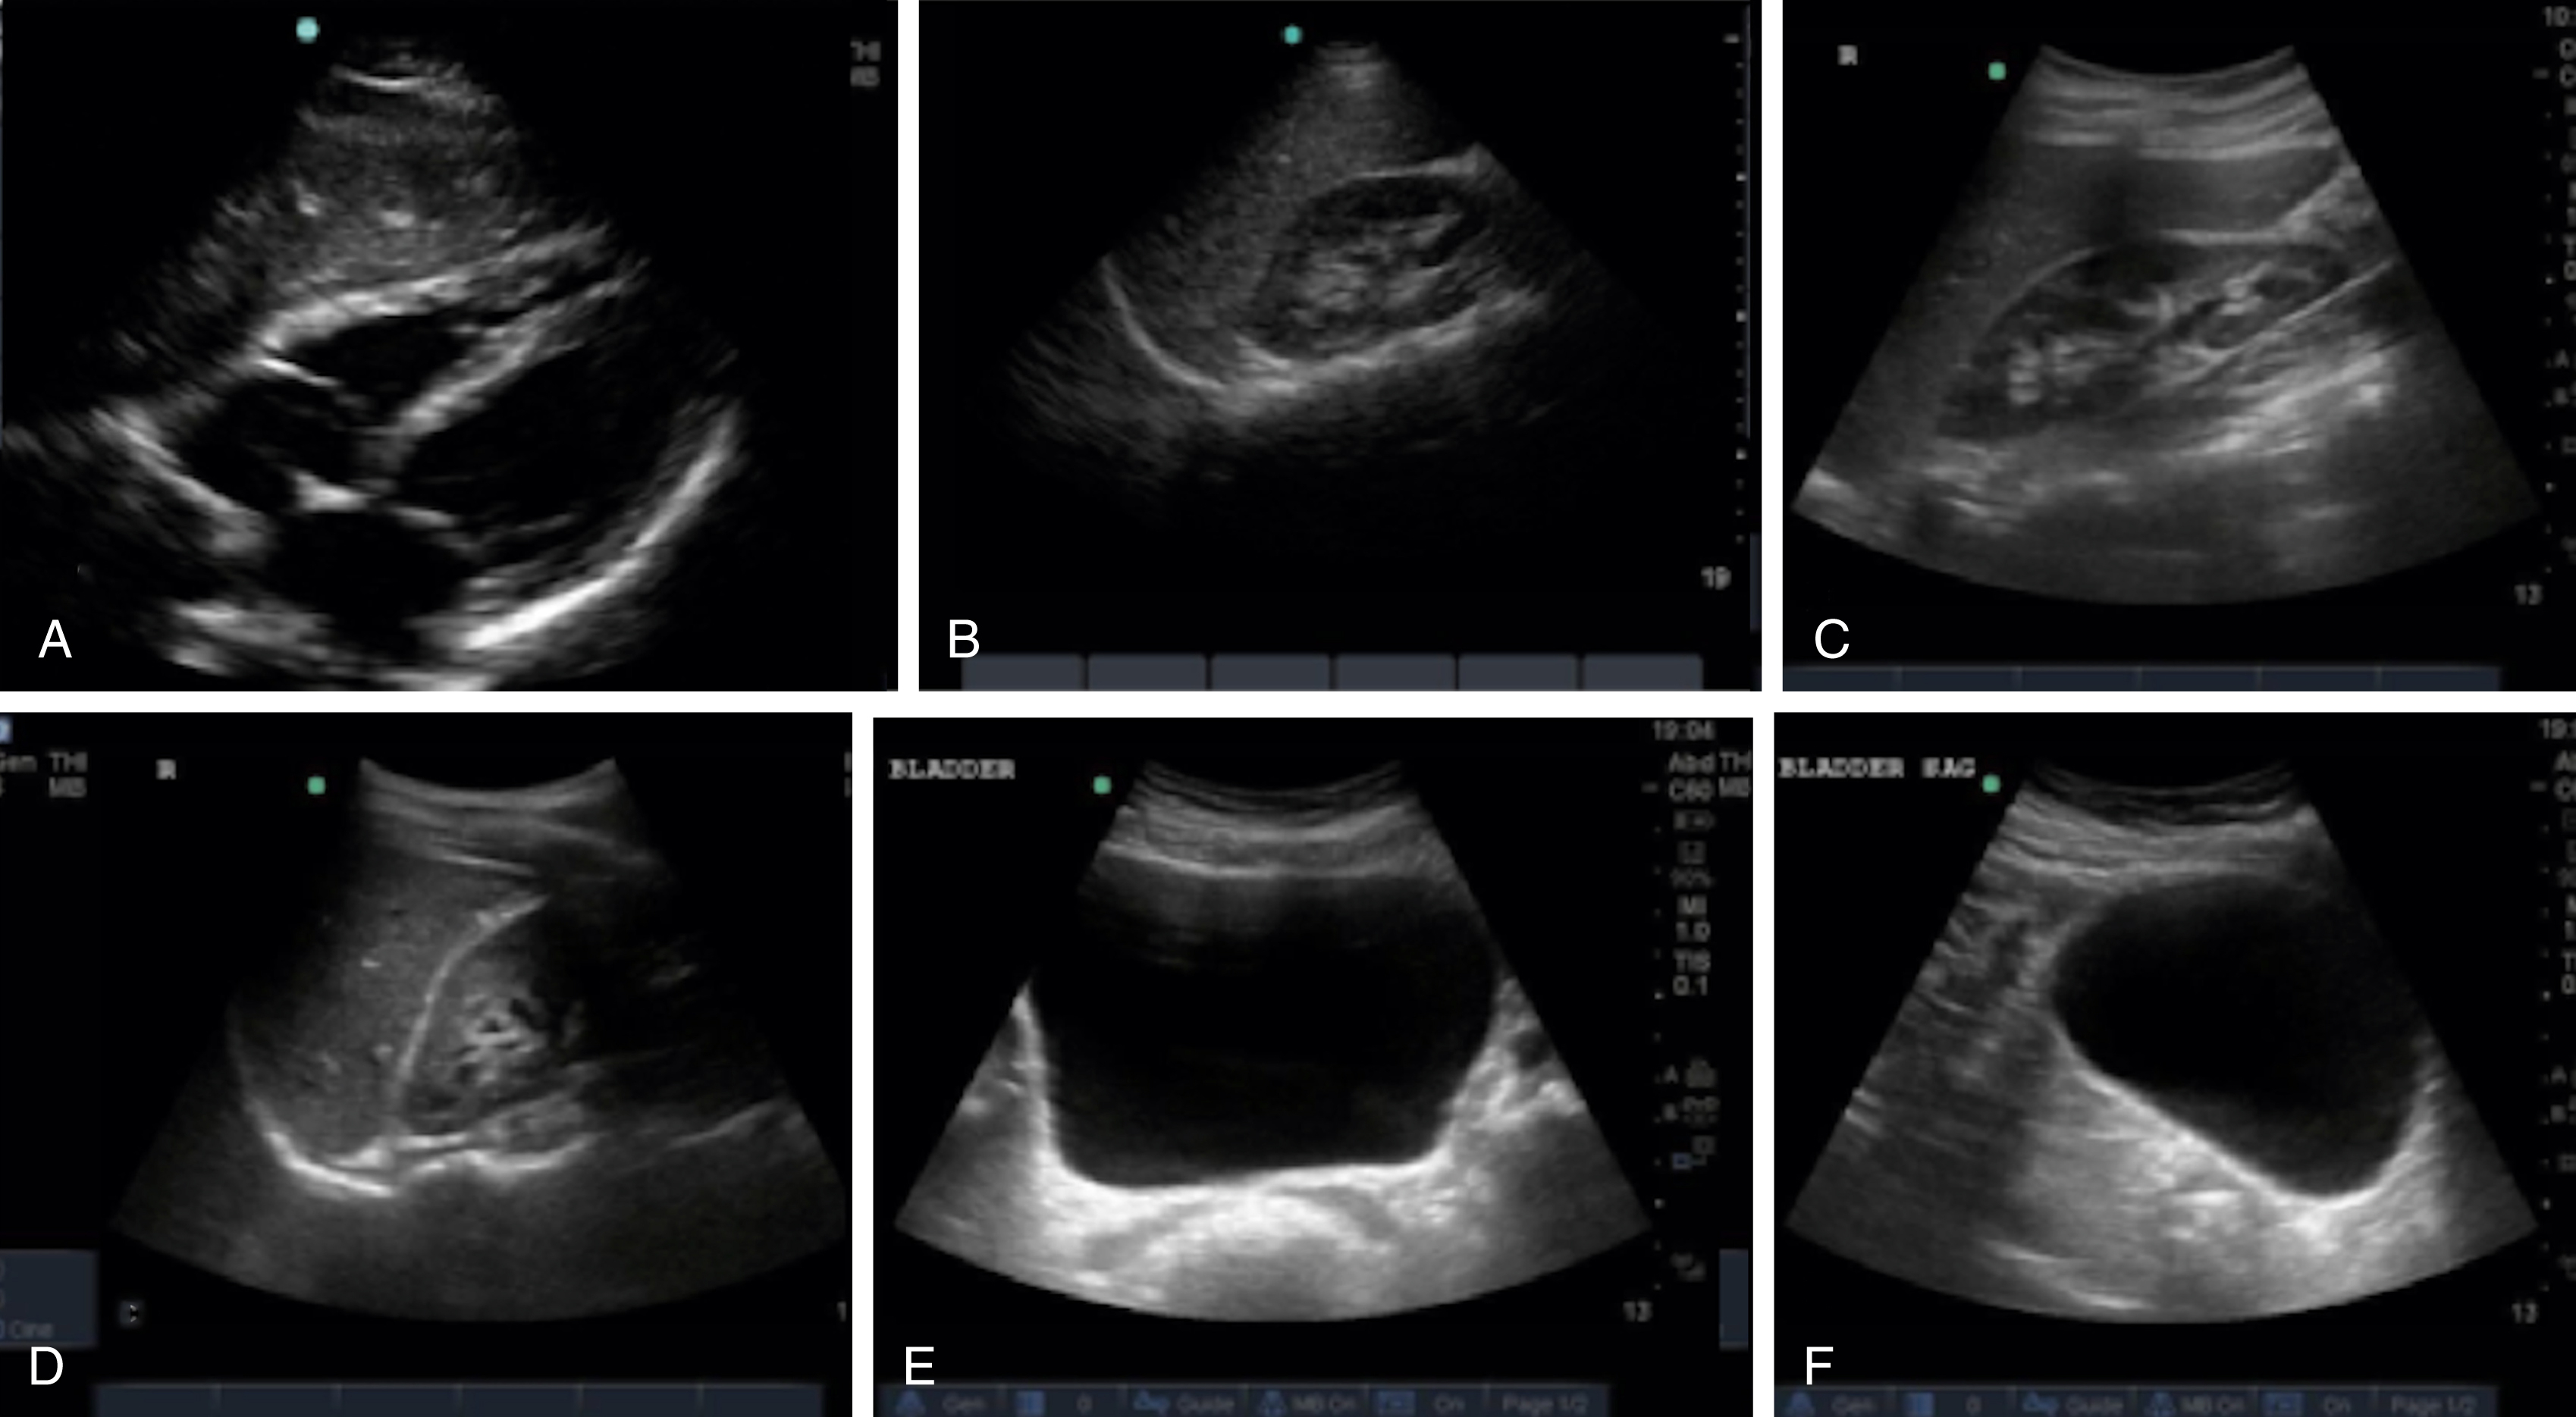

The FAST examination technique uses a low-frequency broadband transducer (2–6 MHz) to evaluate dependent peritoneal spaces, pleural spaces, and the pericardium for free fluid, which in the trauma patient is presumed to be blood. There are four main components of the basic FAST examination: (1) the right upper quadrant (RUQ) view, (2) the left upper quadrant (LUQ) view, (3) the pelvic view and (4) the cardiac view ( Fig. e3.1 ). The E-FAST includes anterior chest views to evaluate for pneumothorax. The RUQ view evaluates for fluid in the thorax (above the diaphragm) ( Video e3.1 ), hepatorenal space (Morison pouch) and the paracolic gutter (inferior edge of the liver and right kidney) ( Video e3.2 ), moving cephalad to caudad. The LUQ view, found slightly more superior and posterior than the RUQ, should mimic the RUQ views, but also include the subdiaphragmatic space, because free intraperitoneal fluid tends to accumulate here initially. The pelvis should be evaluated in the transverse and longitudinal planes, where fluid may be detected deep to the uterus (in females) or in the retrovesical space (in males) ( Video e3.3 ). The cardiac evaluation can be performed in either the subcostal (or subxiphoid) or parasternal window ( Video e3.4 ). Evaluation for pneumothorax uses a low or high-frequency transducer at a shallow depth, placed along the anterior chest wall and will be discussed in more detail in subsequent sections.

Fig. e3.1

Negative FAST images. (A) Subxiphoid view with no pericardial effusion. (B) Negative RUQ view showing the thorax and hepatorenal space without the paracolic gutter visualized. There is mirroring and loss of the spine, indicating a negative thorax. (C) Negative paracolic gutter area by the liver tip in the RUQ view. (D) LUQ view showing negative thorax, as in B, and splenorenal space. (E) Negative transverse bladder view. (F) Negative sagittal bladder view.